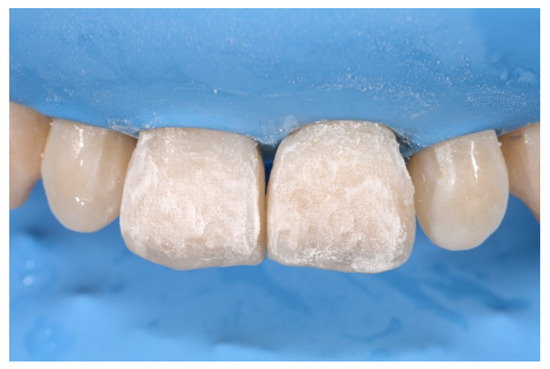

2. Case Presentation

- Molding palatal wall and incisal margin;

- Building interproximal walls with matrices;

- Layering free-hand buccal surface.